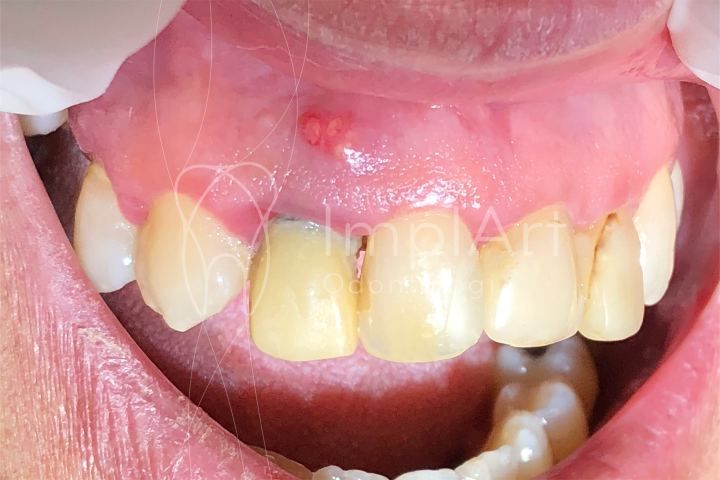

Fístula dental: o que é essa bolinha na gengiva com pús?

Bolinha amarela na gengiva, bolha na gengiva ou bolinha vermelha na gengiva são os principais sintomas de fístula dental. Trata-se de uma reação do organismo por causa de alguma infecção no dente.

A fístula dental é caracterizada pelo surgimento de uma ou mais bolinhas na gengiva, na maioria das vezes de cor amarelada, por reação à uma infecção na região supra gengival. A cor amarelada é, portanto, sinal de acumulo de pus.

Essa condição é comum nos casos de cárie profunda, infecção dos canais, perfuração ou fratura da raiz dentária, periimplantite (infecção em torno de um implante dentário), entre outros motivos.

As lesões são facilmente identificadas pela pessoa em casa e também no consultório. Em geral elas não causam dor, mas é preciso que um dentista avalie para investigar o que está causando esta fístula e tratar o dente e a gengiva e evitar problemas mais sérios, como a perda do dente.